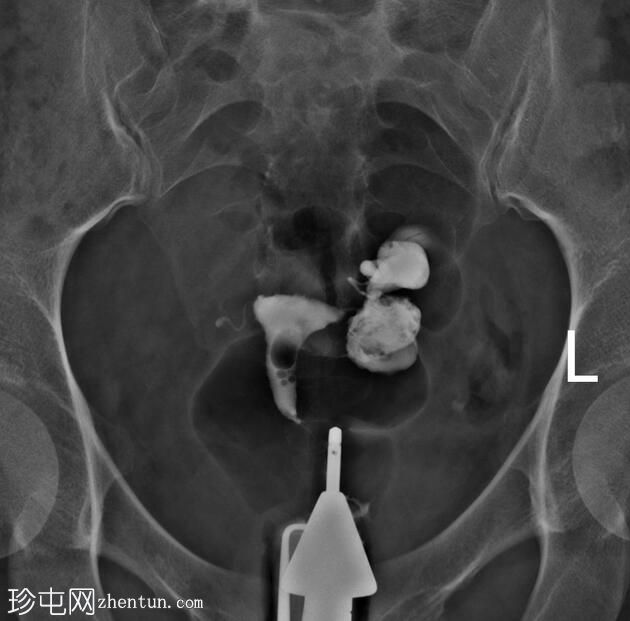

左侧输卵管阻塞和输卵管积水

子宫位于盆腔正中线,形态及轮廓正常。

宫颈管长度及黏膜表面正常,扩张正常。

左侧输卵管充盈,管腔扩张,造影剂残留,无因输卵管积水导致的溢液。

右侧输卵管峡部造影剂显影中断,造影剂远端呈球状扩张。

输卵管积水是指输卵管内充满液体的扩张。